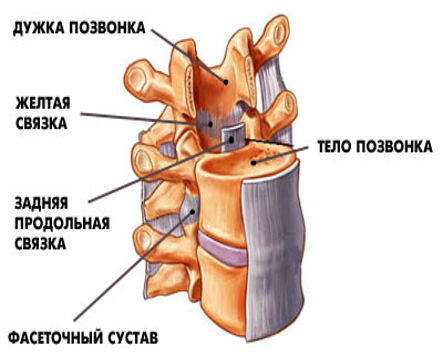

Структура и анатомия синдесмоза: научные иллюстрации